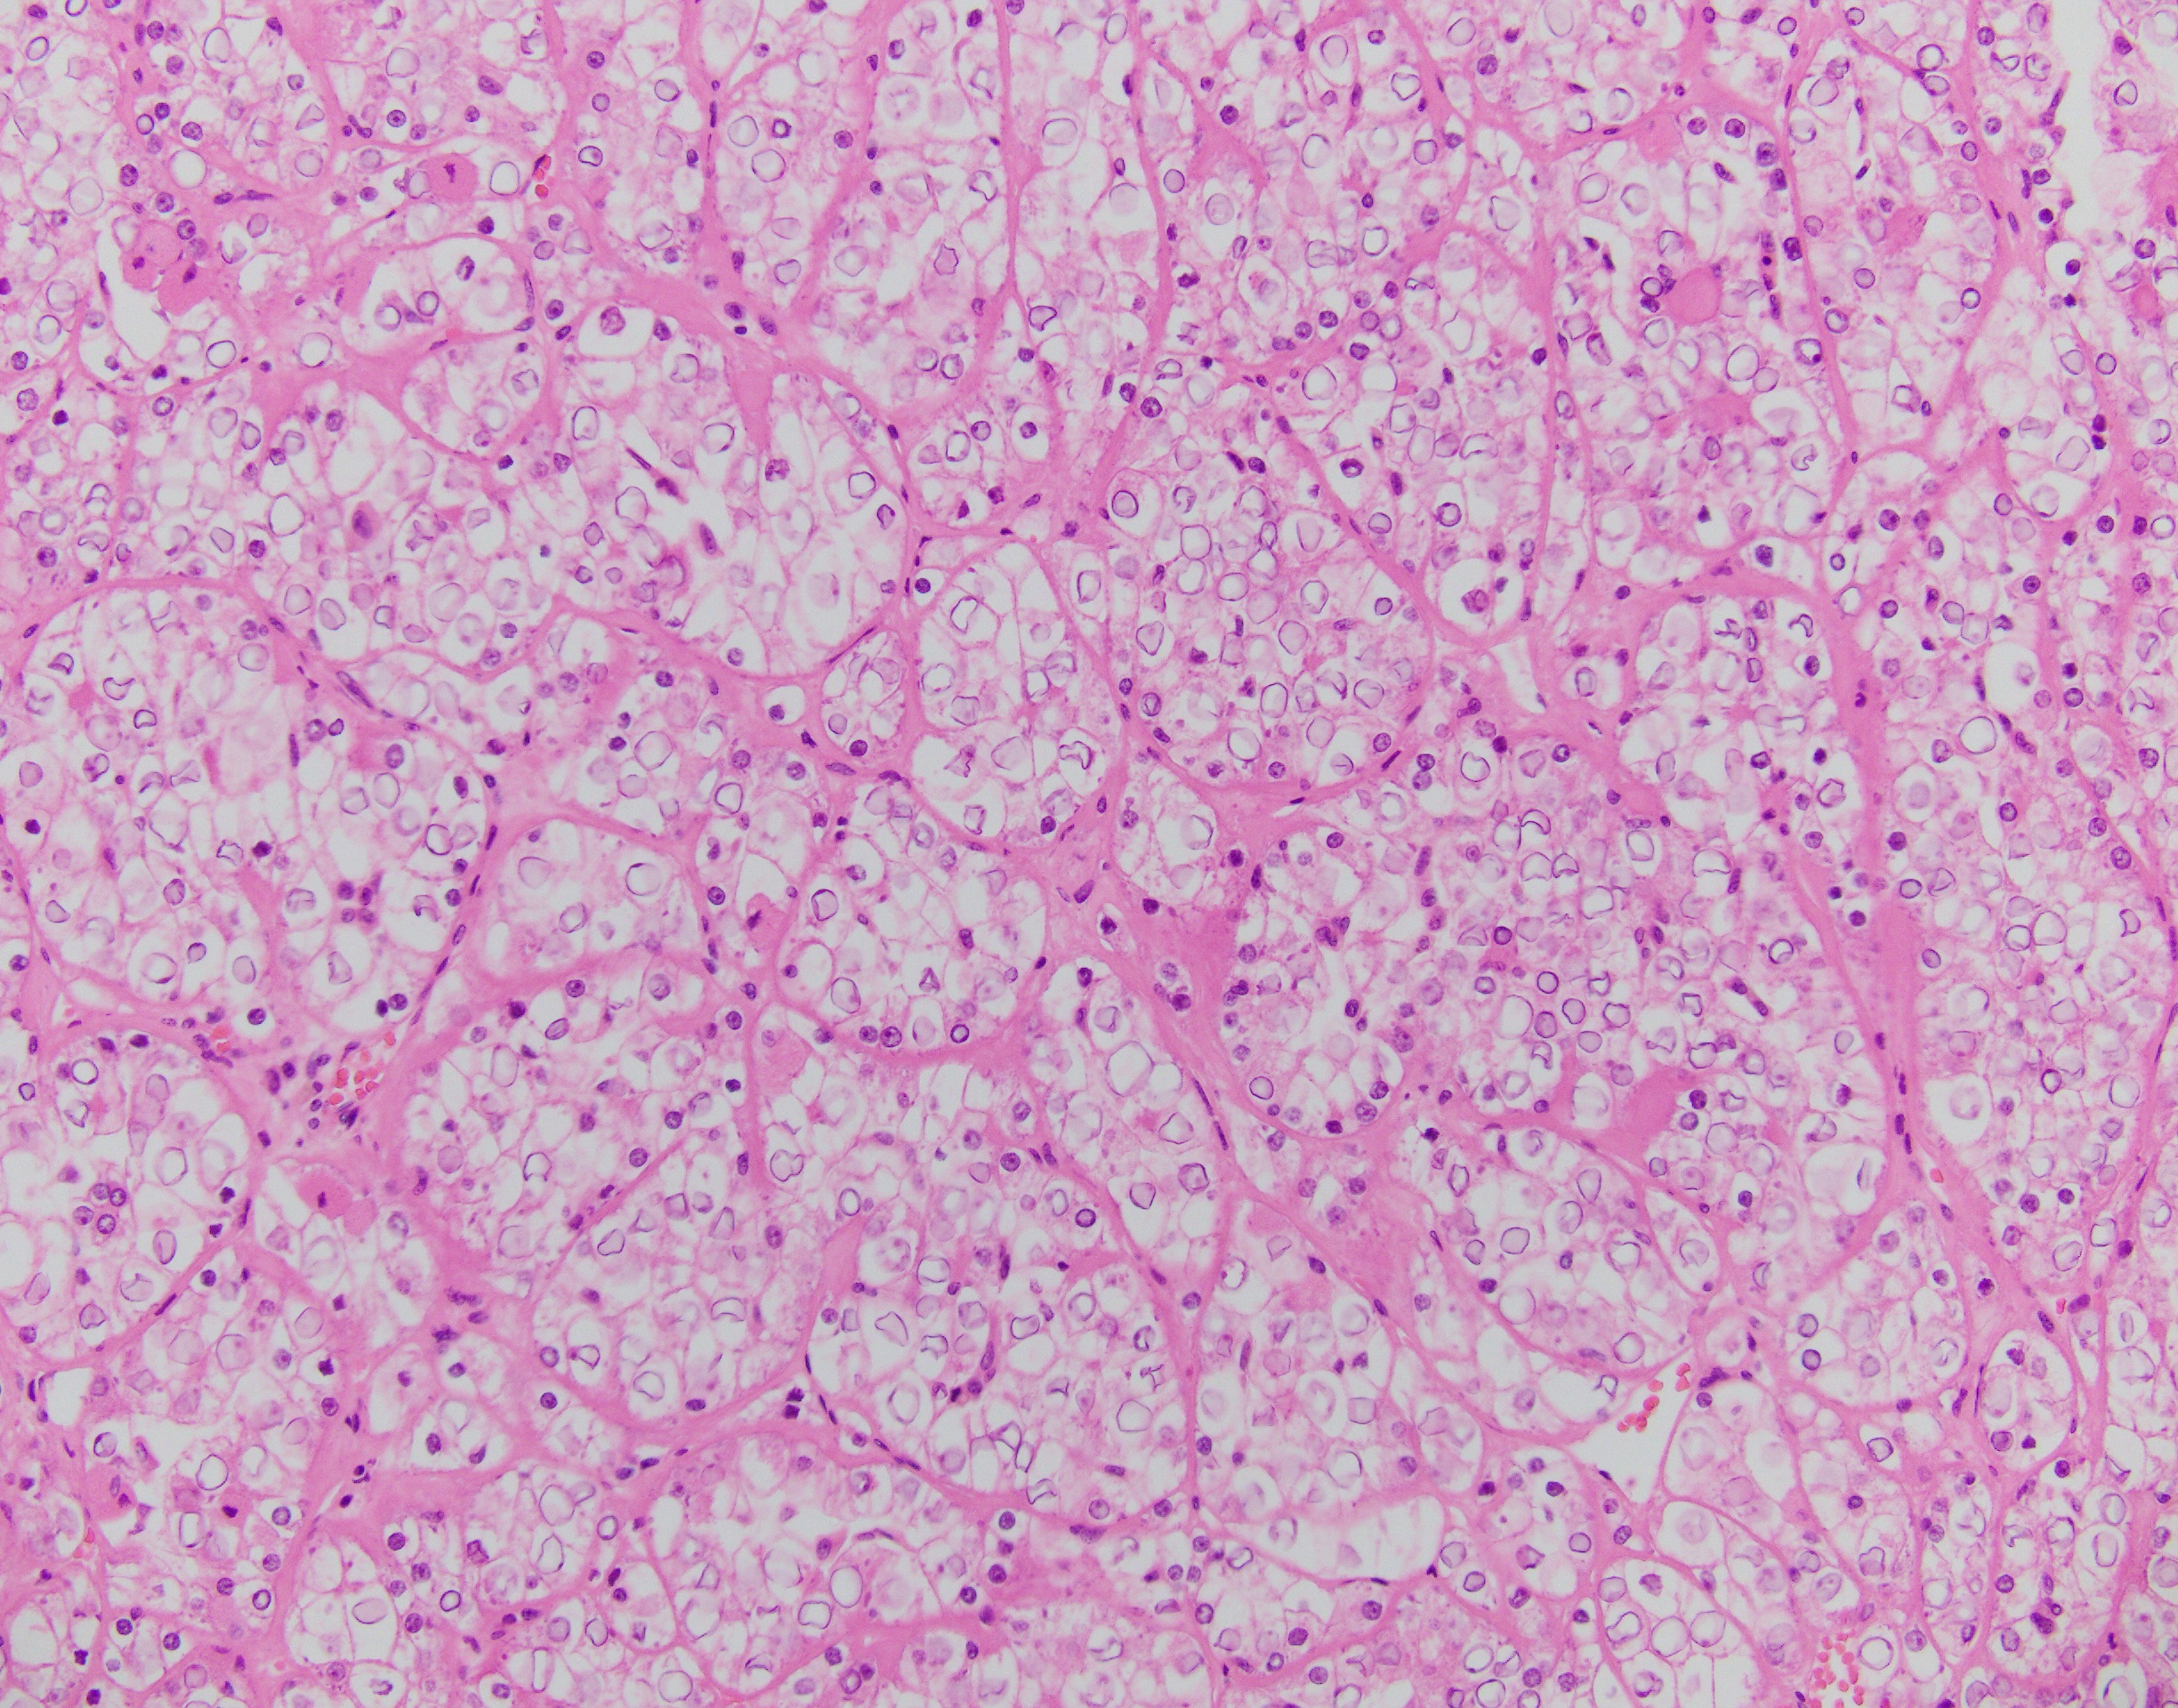

The neoplasm has a compact architectural growth pattern with confluent anastomosing cords, tubules and acini. The tumor cells have granular eosinophilic cytoplasm containing glycogen. The nuclei are round to oval with slightly irregular contours, having a distinct chromatin pattern with condensation at the periphery with clearing of the central portion.

Translocation-associated RCCs involve the MiTF/TFE (Microphthalmia-associated transcription factor/transcription factor binding to IGHM enhancer 3) family genes. The primary genes involved are either TFE3 (located at Xp11.2) or TFEB (located at 6p21.1). Due to the relatively small number of cases studied so far, knowledge of the clinical aspects and outcome of these tumors is not complete. They do represent at least 20% of RCCs in the pediatric age group. Histologically, t(6;11) carcinomas usually consist of nests and microscopic cysts composed of polygonal cells with pale or eosinophilic cytoplasm. Papillae are uncommon. These cells can be arranged around nodules of hyaline material in large acini.